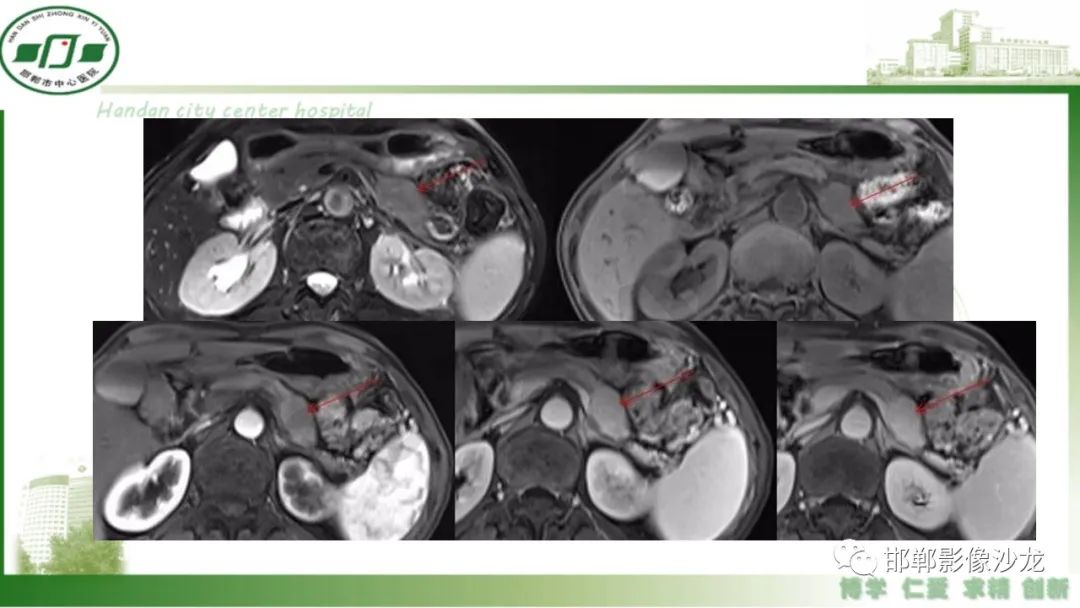

肿块性胰腺炎与胰腺癌的临床、实验室检查、影像学表现有时候很难鉴别,但两者的临床处理、预后又有很大的不同,因此我们平时工作中需要注意两者之间的区别,谨慎诊断,力争为患者及临床带来更大的帮助。